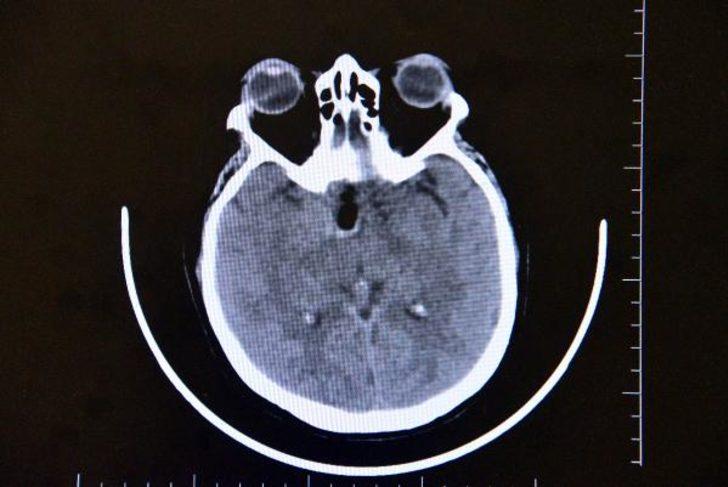

Altun tarafından yapılan muayene ve tetkiklerde Gül'ün beyninde ceviz büyüklüğünde tümör olduğu ve gözündeki sorunun tümörden kaynaklandığı tespit edildi.

Hastamız görme şikayetiyle ilgili birçok yere gitmiş ancak hastalıkla ilgili bir teşhis konulamamış. En son çekilen filminde ana şah damarlarını tamamen saran, görme sinirini tamamen kapatan, solunumla hayat merkezinin önünde geniş bir kitle olması üzerine hasta tarafıma geldi. Hastayı değerlendirdikten sonra endoskopik yöntemle kamera eşliğinde burundan girerek ceviz büyüklüğünde, 3,5 santim genişliğindeki kitleyi almaya karar verdik. Hastamız tüm riskleri kabul etti. Tabi burada önemli olan ana damarlar üzerinde geçmesi, ana damarlarını sarması, görme sinirinin üzerinde olması ve solunum merkezine doğru ilerlemesi bir risk faktörüydü. Biz bununla ilgili gerekli tedbirlerimizi aldıktan sonra ameliyata girdik."

"Ameliyatta başarılı bir şekilde gerçekleşti, herhangi bir görme sinirinde, ana damarlara veya solunum hayat merkezine dokunmadan tümörü tamamen burundan temizledik. Hastamız gayet iyi rahat. Beynin orta yerinde taban bölgesinde dediğimiz, 3,5 santim ebadında, ceviz büyüklüğündeki tümörümüz solunum hayat merkezinin önünü kaplaması ve oraya doğru ilerlemesi,sağ ana damarlara doğru ilerleyip tamamen içerine alması ve hipofiz bezini alttan yukarı doğru sarması, bu ebada ulaşması milyonda bir oranda gözükür. Biz bu tümörü, burundan girilerek endoskopik yöntemle tamamen ana damarlara herhangi bir zarar vermeden çıkarttık.''